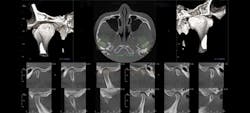

Dr. Majors reviews a cone beam image to consider available treatment options for a new patient.

When my assistant takes a scan, I can look-immediately, and before the patient is even reseated in his or her room, I can say, "Yes, we can do this," or, "No, we can't." To have greater efficiency and clarity courtesy of one technology is incredible.